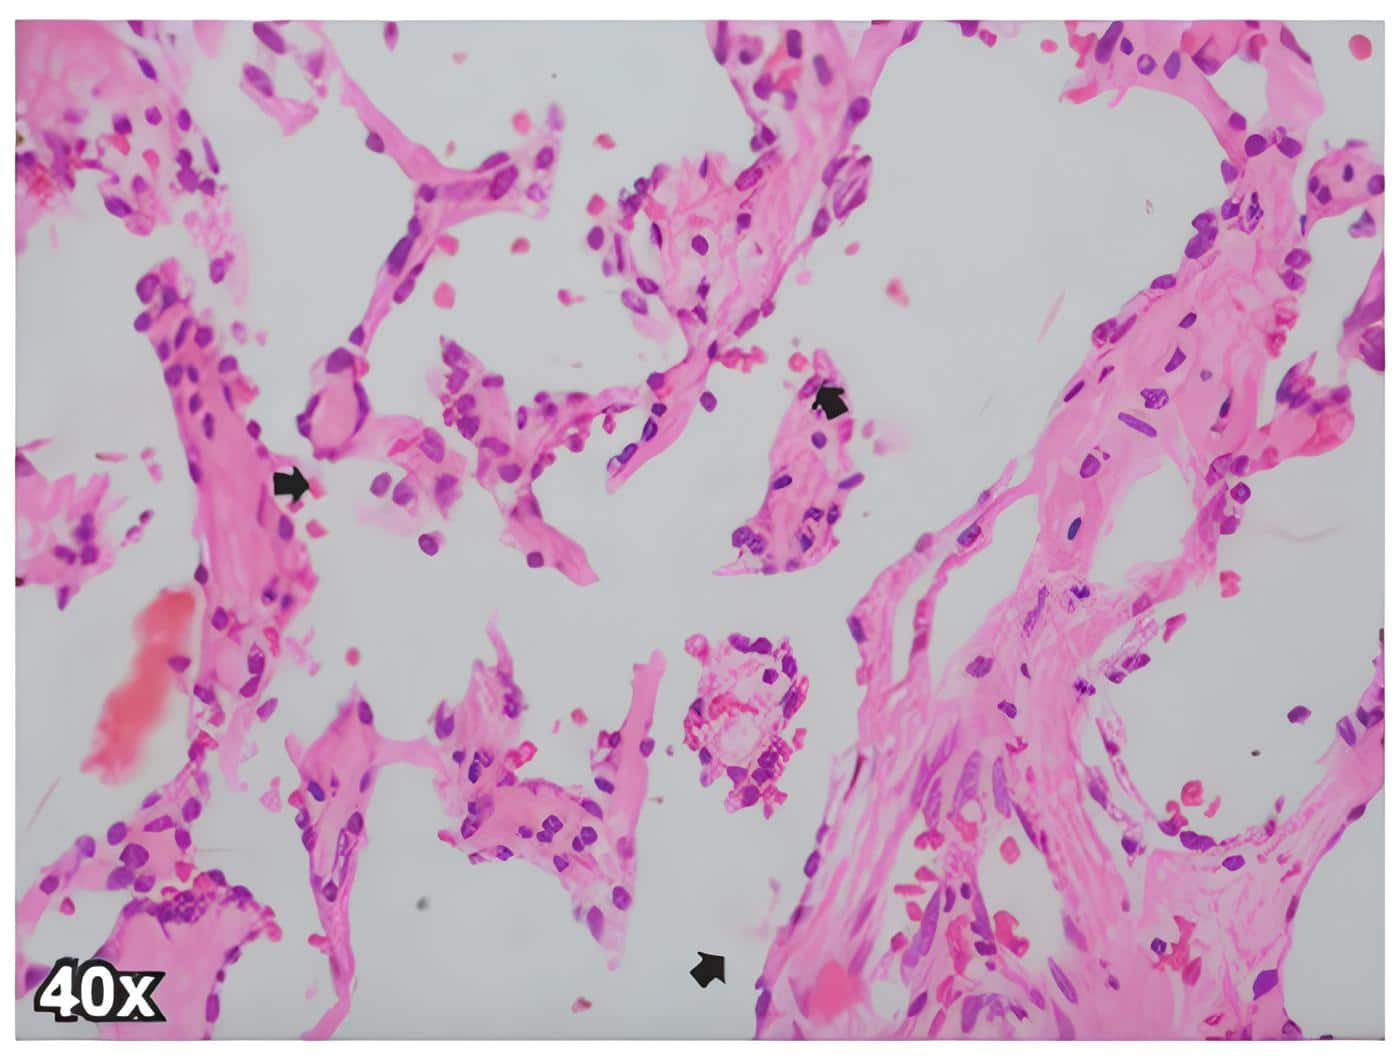

En el control a los 20 días del procedimiento quirúrgico, se entregó reporte de patología donde se confirmaba el diagnostico oncológico de angiosarcoma de mama de bajo grado, ya que en los cortes de hematoxilina y eosina se identificó una lesión tumoral constituida por canales vasculares anastomosados, extravasación de eritrocitos estromales y células endoteliales con hipercromasia nuclear leve (Figuras 1 y 2), con positividad para los marcadores de inmunohistoquimica CD34 y ERG (Figura 3).

Figura 2. Corte del angiosarcoma de mama de la paciente, donde se observan celulas endoteliales

con hipercromasia nuclear leve (flechas negra). Tincion de hematoxilina y eosina 40x.